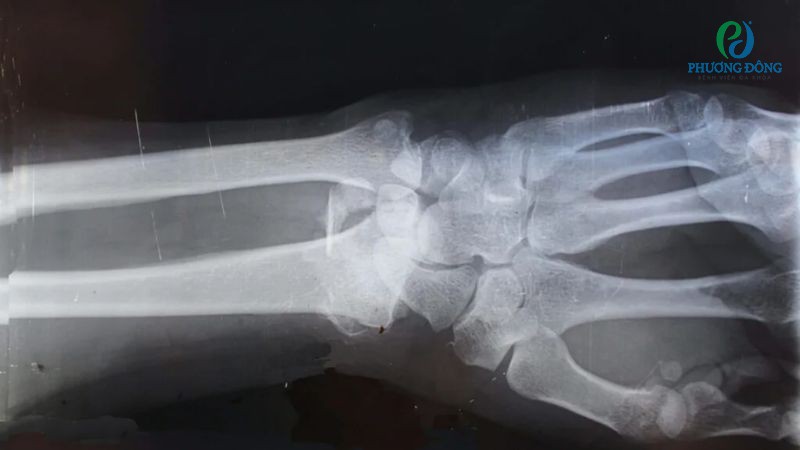

Trường hợp nghi ngờ có tổn thương khác đi kèm, bác sĩ sẽ chỉ định thêm một số xét nghiệm hình ảnh khác:

- Chụp X-quang cổ tay nhằm loại trừ vấn đề gãy xương, đặc biệt xương thuyền. Đánh giá khớp quay, khớp thang, khớp giữa các xương cổ tay, phát hiện sự xuất hiện của gai xương hoặc tiêu xương.